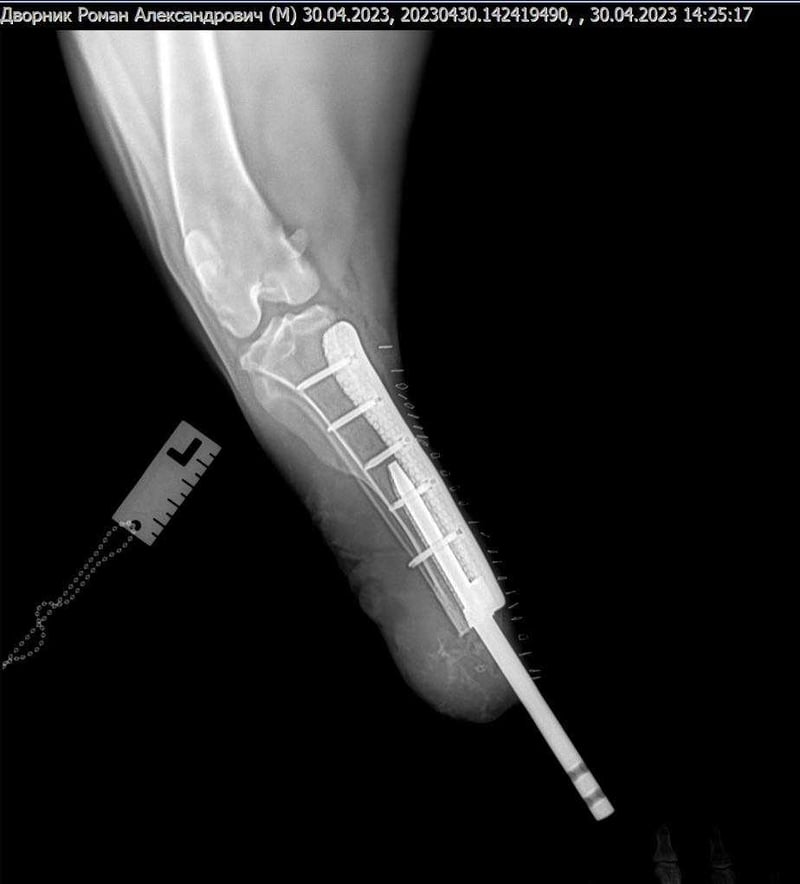

«Хотів представити перше в Харкові біоінтегроване протезування кінцівки у собаки, та ще вагою 56 кг», — повідомив лікар.

Операція пройшла на базі Салтівської ветеринарної клініки філіалу «Харківського ветеринарного госпіталю».

Імплант розробили за допомогою принтера на основі тривимірної комп’ютерної моделі 3D metal tech.